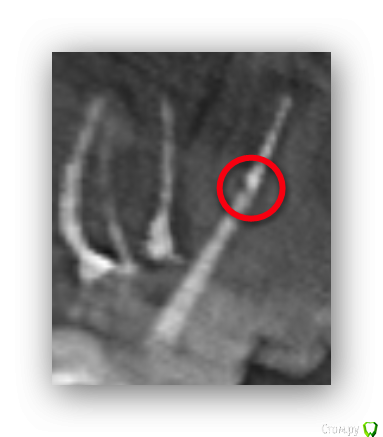

freeman22 Опубликовано 27 октября, 2015 Автор Поделиться Опубликовано 27 октября, 2015 Посмотрите пожалуйста ещё под этой проекцией, там всё нормально (где я выделил)? http://s017.radikal.ru/i401/1510/41/87acd0687e83.pnghttp://s013.radikal.ru/i324/1510/3e/028a8af12ff7.png Ссылка на комментарий

DmitrySH Опубликовано 27 октября, 2015 Поделиться Опубликовано 27 октября, 2015 Что Вас беспокоит? Ссылка на комментарий